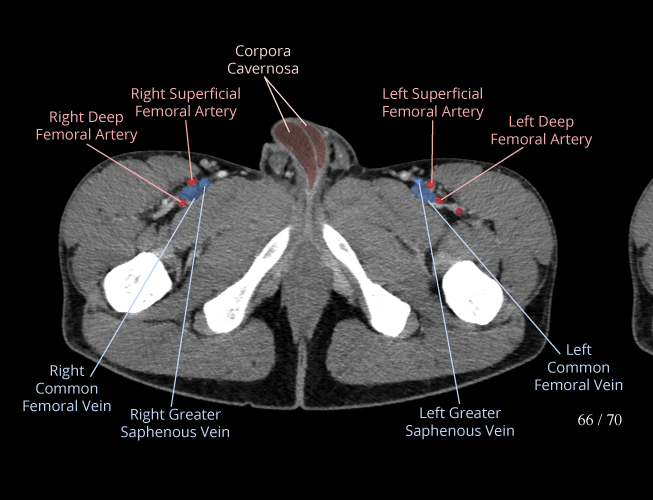

Body

Covers abdominal CT anatomy.